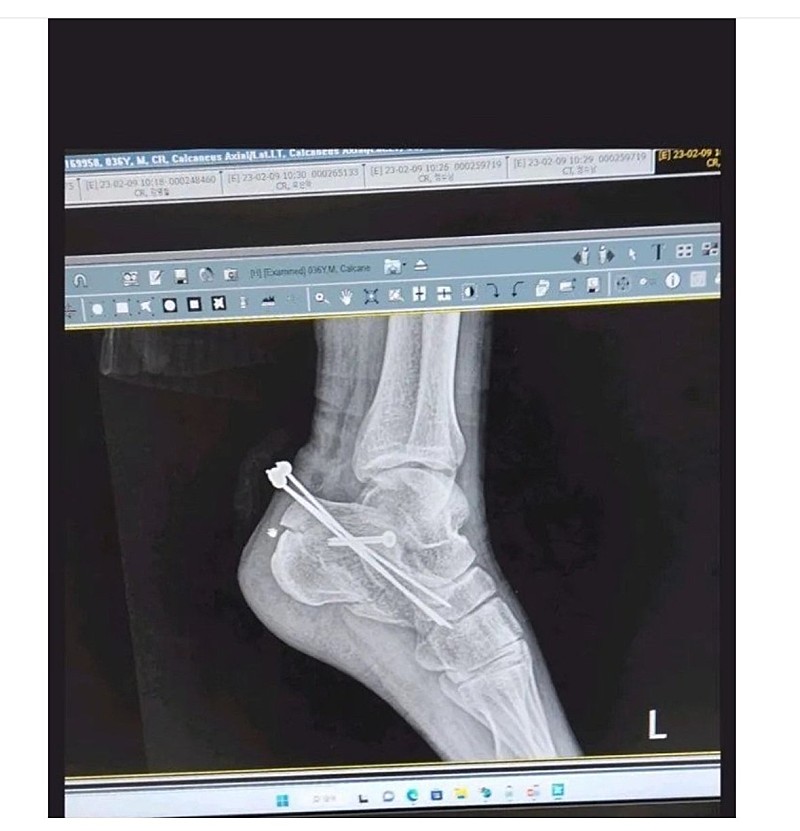

집에서 손으로 철심 뺀 사람